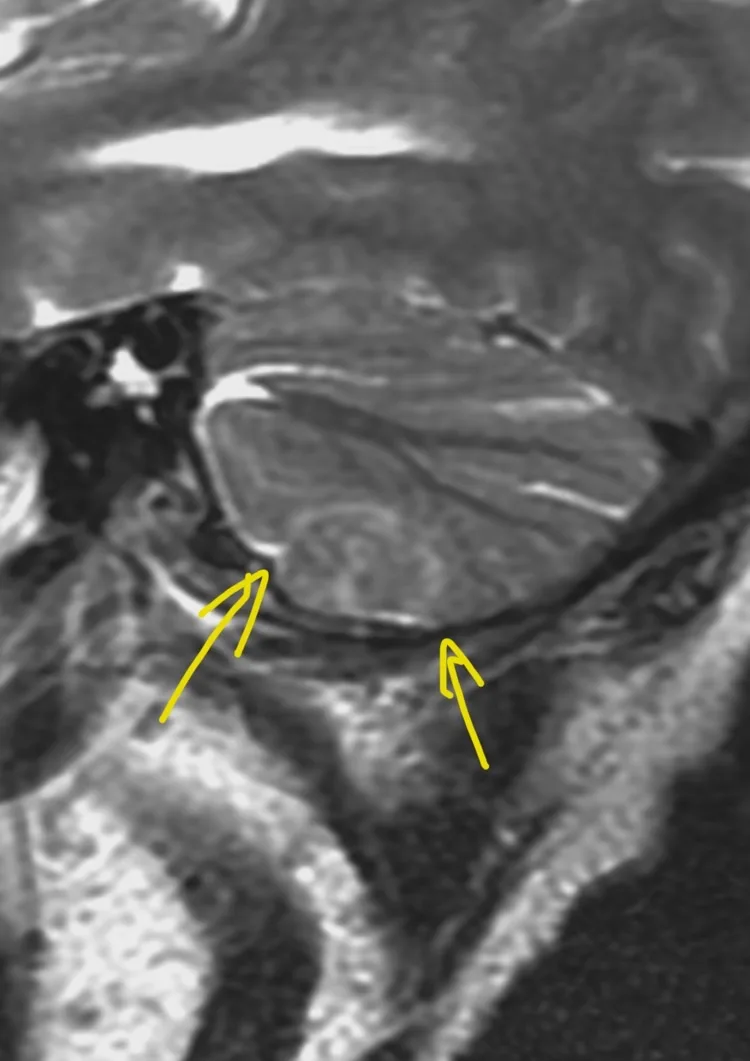

Менингиомы иногда не ходят одни. А по две, три и больше. Самая крупная слева в ЗЧЯ - хорошо видно место, из которого она растет: фокальные утолщения кости по краям и плоское основание опухоли (стрелки).